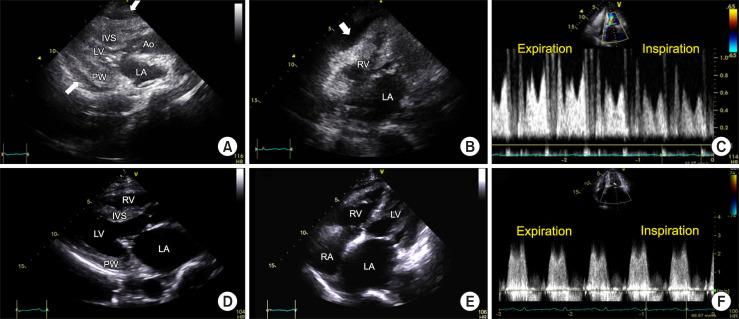

Fatal Myopericarditis in a Patient With Lupus Erythematosus Supported by Extracorporeal Membrane Oxygenation: A Case Report.

Systemic lupus erythematosus (SLE) may occur in any organ. In patients with SLE, myocarditis is extremely rare and potentially life-threatening. Herein, we report on a patient with lupus myocarditis, diagnosed by myocardial biopsy, immunologic tests, and clinical manifestations. Our findings suggest that securing time for diagnosis via extracorporeal membrane oxygenation and other intensive care is helpful for obtaining a good prognosis.